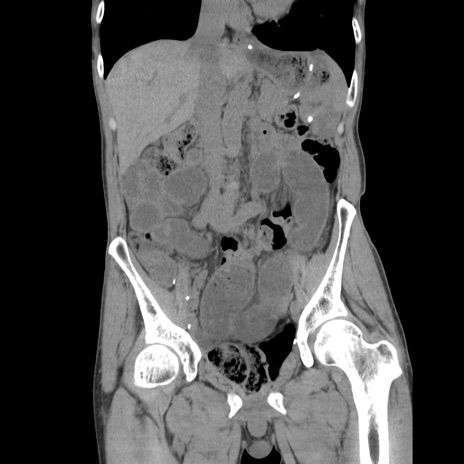

症例11(冠状断像)

【症例】 60歳代男性

【主訴】 下腹部痛

【現病歴】 本日夜中より下腹部痛の症状認め、受診。

【既往歴】 膀胱癌(膀胱全摘+尿管皮膚瘻術) 、胃癌術後

【身体所見】 BT 35.3℃、PR 58/min、BP 136/98mHg、腹部平坦、軟、腸蠕動音±、ストマ留置あり、左上腹部~正中部に圧痛あり、反跳痛なし。

【データ】WBC 5100、CRP0.01

横断像